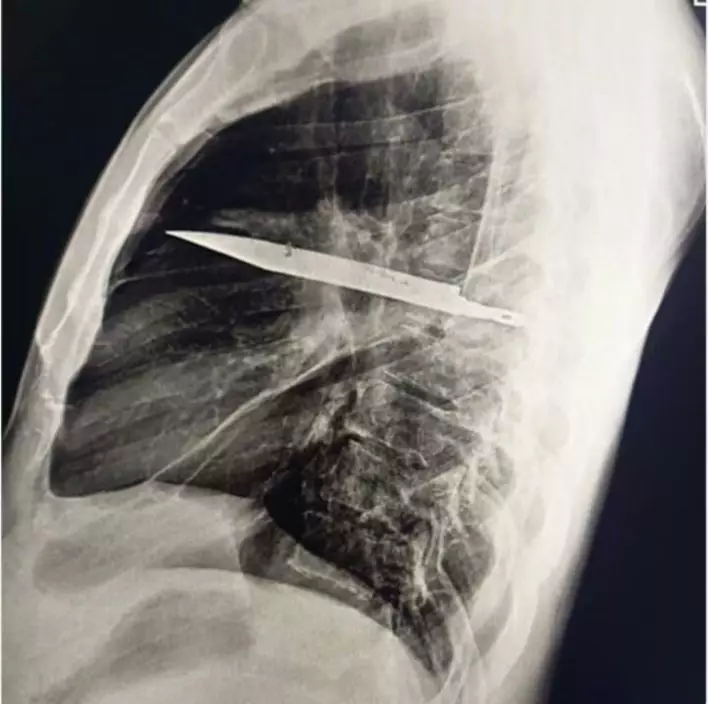

醫生隨後為男子安排X光檢查,結果發現胸腔內竟藏有一件利刃狀金屬異物,自肩胛骨位置刺入,四周被膿液及壞死組織包圍,令醫療團隊大為震驚。在醫生追問下,患者回憶起 8 年前曾捲入一場激烈衝突,當時臉部、背部、胸部及腹部均遭多處刀傷。然而,由於當地醫療資源匱乏,他僅接受表層傷口縫合,並無進行深入檢查,之後多年也未曾出現異常症狀。

經專科安排,男子立即接受手術移除刀片,術後恢復情況理想,於 10 天後順利出院。醫療團隊表示,「患者身體成功將異物包覆在纖維囊內,限制了發炎和組織損傷」,但乳頭開始流膿已是嚴重併發症前兆。他們強調,這枚殘留刀片原可造成致命風險,並呼籲提升資源不足地區的創傷處理能力及醫療設備,以免類似情況再度發生。目前,相關病例已刊載於《外科病例報告期刊》(JSCR)。